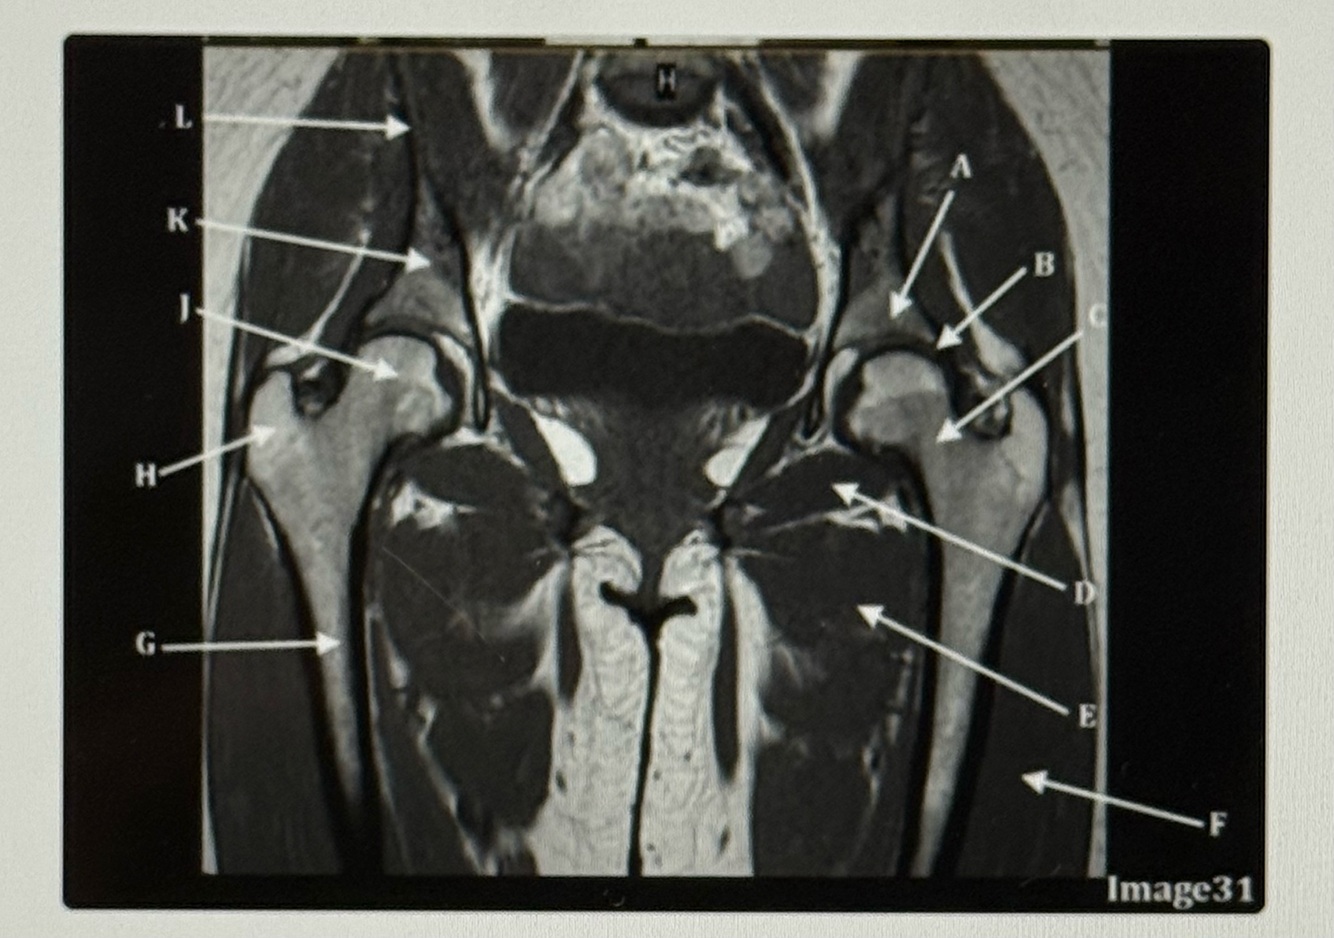

Letter A points to the

Acetabulum

Letter B points to the

Labrum

Letter C points to the

Femoral neck

Letter D points to the

Obturator externus

Letter E points to the

Adductor muscles

Letter F points to the

Vastus lateralis

Letter G points to the

Femur

Letter H is pointing to the

Greater trochanter

Letter J points to the

Femoral head

Letter K points to the

Body of the ilium

Q

Letter L points to the